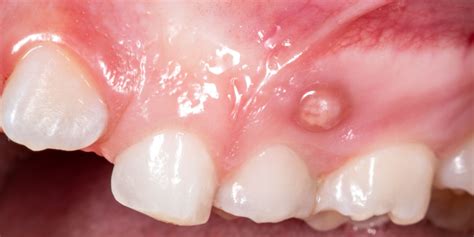

Cabe señalar que puedes padecer una fístula dental sin dolor. La presencia de una fístula no tiene porqué ir asociada con dolor, por ello se puede sentir la tentación de ignorar esa fístula dental. Son protuberancias que salen en la zona de las encías y que, aunque se inflaman, no siempre duelen.

- Dolor e inflamación: Una de las primeras señales de una fístula dental es el dolor en la zona afectada. El dolor es uno de los síntomas más característicos de una fístula dental. Puede manifestarse como un dolor punzante, pulsátil o constante en el área del diente afectado. Este dolor puede empeorar al masticar, hablar o aplicar presión sobre el diente comprometido. La infección en la raíz del diente puede provocar sensibilidad al calor y al frío, así como dolor constante o punzante. Al principio, las encías se inflaman ligeramente y enrojecen. Con el tiempo, la fístula dental se llena de pus y aparece un dolor punzante.

- Abscesos dentales: La presencia de una fístula dental puede dar lugar a la formación de abscesos dentales. Un absceso dental es una acumulación de pus causada por una infección bacteriana en el tejido dental. En el caso de una fístula dental, el absceso puede manifestarse como una protuberancia roja y dolorosa en las encías cerca del diente afectado. Esta protuberancia puede estar acompañada de sensibilidad al tacto y al calor, así como de hinchazón en el área circundante.